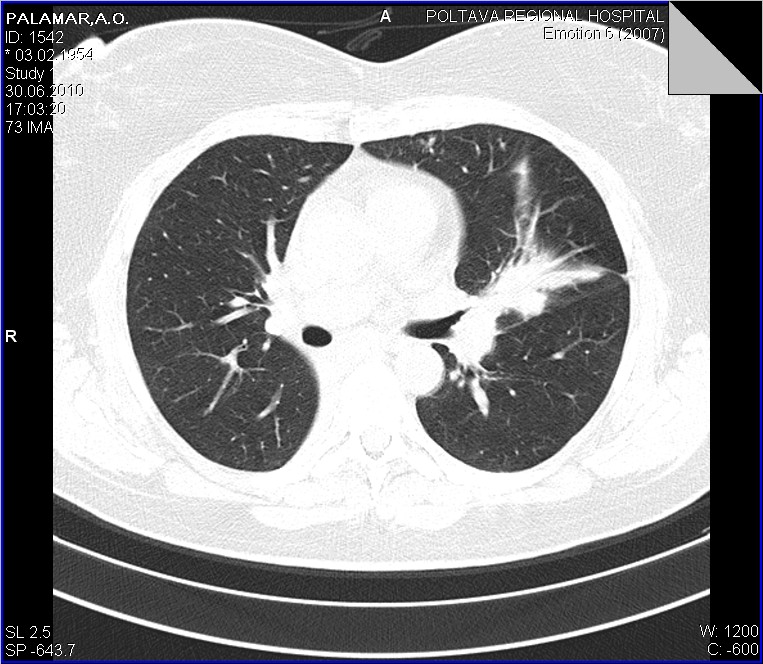

Беседую с пациенткой...да кишечные проблемы были, уже прошли...около 6-8 ми месяцев назад болеела (основная жалоба - кашель), лечилась, в т.ч. стационарно, обследовалась, в т.ч  КТ в ООД - сказали все нормально...живите мол и дальше. Данные предыдущих исследований обещают доставить с понедельника, будем и сами ее докручивать. Ваше мнение, коллеги?

На первых репродукциях рентгенограмм мне виделся ателектаз S7, S8. Теперь вижу: спалось всё, кроме S6. И насчёт средней доли не согласен я: картина в боковой проекции была бы другая – классическая! Но корни надежды не оставляют.

Повторюсь еще раз со сканами, несколько полнее. Конечно, это уже не столь принципиально, но, как по мне, ни С6, ни средней доли нет...Давайте просмотрим еще раз.

Со сканами-то ясность полная. Нет бронха средней доли и шестого. Метод, конечно, превосходный, но и качество снимков имеет огромное значение.

1.Плеврит, как рабочий диагноз тоже пристутсвовал

2. Никтои не спорит, что он, в какой то мере есть, о незначительном количестве "густой" жидкости говорят и УЗИсты

3. Но куда деть "культю" промежуточного бронха? и при чем тогда тут (по отношению к культе) плеврит? Неужели он в состоянии сдавить такой бронх?

1. Спасибо за ссылку, одна из "картинок" полностью повторяет выставленной наблюдение. 2. А теперь о "гвозде", который мне забили пять минут назад "между глазиков". После того, как я переколотил всю хирургию, последняя взялась рьяно выяснять все о больной. Имеется у нее рак матки 4-й степени, состоит она на учете в ООД по этому поводу, все остальные изменения вторичные..... Вот такой случай с ургентности...или о приемственности в наше время...